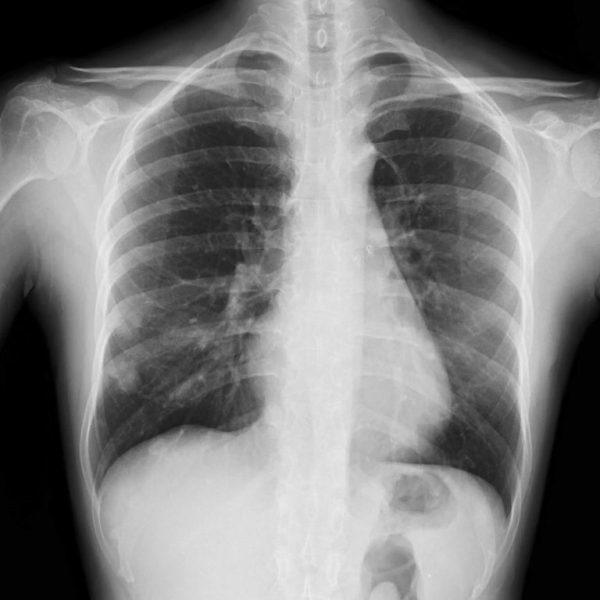

コニカミノルタはデジタルX線動態撮影および動態解析を、新しい“動きの診断”を提供するソリューションとして展開している。この同社独自の技術「X線動態解析」を搭載したシステムとして、一般X線撮影装置を用いて動画を撮影できるデジタルX線動態撮影システムを開発・提供しており、既に国内外の医療機関で導入実績がある。